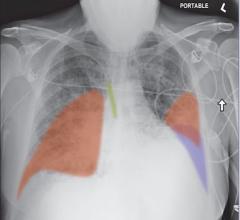

May 5, 2021 — Lung cancer is the third most common cancer in the U.S. and the leading cause of cancer death, with about ...

April 30, 2021 — For many patients with localized lung cancer (non-small-cell lung carcinoma and small cell lung ...